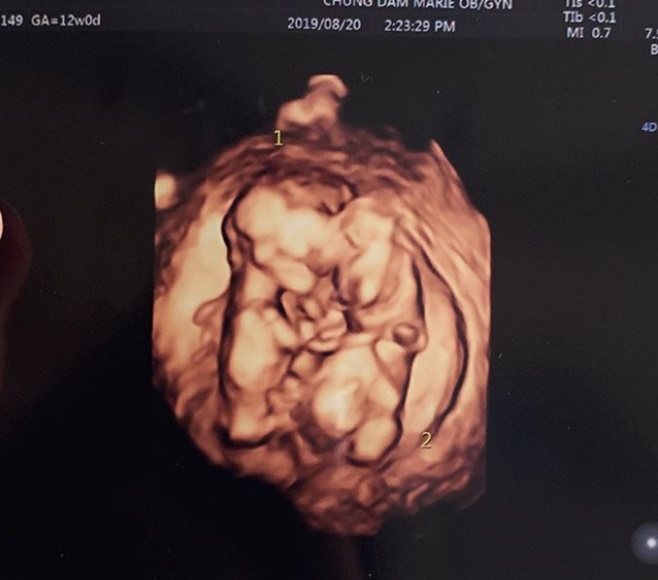

[ƼºêÀ̵¥Àϸ® ±è¿¹³ª ±âÀÚ] ±×·ì ¶óºÕ Ãâ½Å À²Èñ°¡ ½ÖµÕÀÌ ÀӽŠ¼Ò°¨À» ÀüÇß´Ù. À²Èñ´Â 29ÀÏ ÀÚ½ÅÀÇ ÀνºÅ¸±×·¥À» ÅëÇØ "¯ÀÌÀÇ ½ÖµÕÀÌ µ¿»ýµé ¼Ò½Ä µè°í ¸¹Àº ºÐµé²²¼ ÃàÇÏÇØÁּż ³Ê¹« °¨»çÇÕ´Ï´Ù"°í Àλ縦 ³²°å´Ù. µ¡ºÙ¿© À²Èñ´Â "¿äÁò ÀÔµ¡ÀÌ ³Ê¹«³Ê¹« ½ÉÇØ¼ Á¤½ÅÀ» ¸øÂ÷¸®°í Àִµ¥ ±×¸¸Å ±× ´©±¸º¸´Ù °í»ýÇØÁÖ´Â ³²Æí°ú ¾î¸Ó´Ô ´öºÐ¿¡ º°Å» ¾øÀÌ ÇູÇÏ°Ô Å±³ ÁßÀÌ´Ù"°í ±ÙȲÀ» ÀüÇß´Ù. ¶Ç À²Èñ´Â ½ÖµÕÀÌ ÃÊÀ½ÆÄ »çÁøÀ» ÇÔ²² °ø°³Çϸç "µÕÀ̵éÀº ÀÌ·¸°Ô ¼·Î ²À ºÙ¾î Àß Å©°í ÀÖ´ä´Ï´Ù. ´Ù½Ã ÇÑ ¹ø ÃàÇÏÇØÁּż °¨»çµå·Á¿ä"¶ó°í °í¸¶¿î ¸¶À½À» µå·¯³Â´Ù. ÇÑÆí À²Èñ´Â Áö³ 28ÀÏ ¹æ¼ÛµÈ KBS2 ¿¹´ÉÇÁ·Î±×·¥ '»ì¸²ÇÏ´Â ³²ÀÚµé2'¿¡¼ ³²Æí ÃÖ¹Îȯ°ú ÇÔ²² ÀÓ½ÅÀ» È®ÀÎÇÏ´Â ¸ð½ÀÀÌ ±×·ÁÁ³´Ù. ƯÈ÷ ÃÊÀ½ÆÄ °Ë»ç °úÁ¤¿¡¼ ½ÖµÕÀÌ ÀÓ½ÅÀÓÀ» È®ÀÎÇß°í, µÎ »ç¶÷Àº Å©°Ô ±â»µÇÏ¸ç ¹÷Âù ¸¶À½À» Ç¥ÇöÇß´Ù.